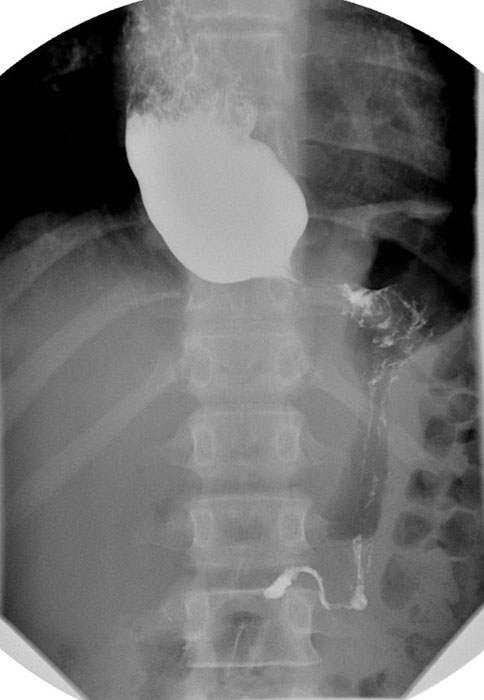

What may be seen on chest X-ray with a large hiatus hernia?

Retrocardiac soft-tissue mass with an air-fluid level.

How do you differentiate the esophagus from the stomach on a barium study?

Esophagus = smooth; stomach = rugal folds.

What is the key landmark to identify in a hiatus hernia?

Diaphragm.